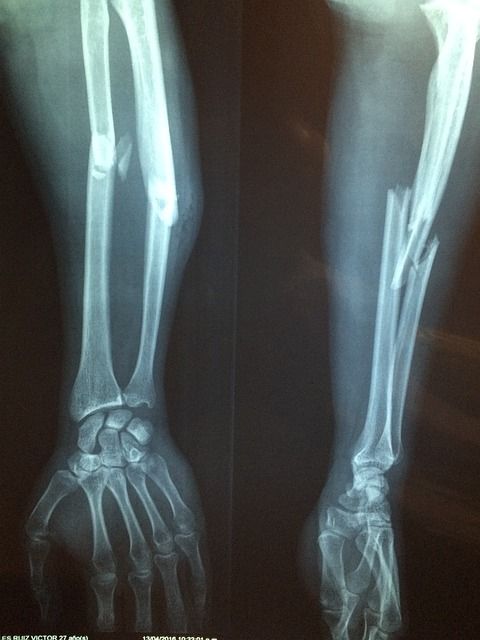

영상 검사

엑스레이와 초음파 검사도 진단에 유용합니다. 엑스레이는 관절의 손상 정도를 파악하는 데 도움을 주며, 초음파 검사는 요산 결정을 시각적으로 확인할 수 있도록 도와줍니다. 이러한 도구들을 통해 관절의 상태나 구조적인 이상을 확인할 수 있습니다.